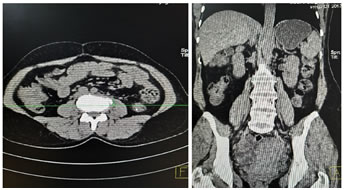

Investigations include complete blood count, differential count, C reactive protein, ESR, urine routine and culture, blood culture, renal and liver function tests, vaginal and endocervical swabs. Ultrasound is the first line investigation for radiological diagnosis, however the diagnosis is often missed because of lack of clinical suspicion. Even with clinical suspicion, it is diagnostic in only 60% of cases 6. Sonography is also essential to rule out the evidence of any retained products of conception. Simple abdomen radiography can demonstrate blurring of the psoas muscle region, and air enhancing duodenal or renal contour, although its diagnostic value for psoas abscess is restricted . The sacroiliac joint, the lumbar spine, and intervertebral disks should be carefully examined. If a lesion is too small to reveal soft tissue gas, spinal destruction, mass effects or unusual iliopsoas, plain films would only reveal negative findings 7. CT is the most accurate investigation for diagnosis of iliopsoas abscess with reported sensitivity of 100% and specificity of 77% 8. Few studies state that the magnetic resonance imaging (MRI) can differentiate soft tissues more accurately, producing a clear view of the abscess wall and its surrounding structures without the use of a radiocontrast agent, thus, making the MRI a better choice than the CT scan 9. On CT scans, an abscess may manifest as enlargement of the iliopsoas muscle by a low-attenuation lesion [FIG 1, FIG 2]. The lesion typically displays rim enhancement after the intravenous administration of contrast material . Abscesses appear as areas of low signal intensity at nonenhanced T1-weighted MR imaging and as areas of high signal intensity at nonenhanced T2-weighted MR imaging [FIG 3]10. Secondary findings include obliteration of the surrounding fascial planes, bone destruction, and gas bubbles. CT is more sensitive than MR imaging for demonstrating gas bubbles.11

Figure 1: Coronal and Axial CT images showing normal appearance of bilateral psoas muscles which show uniform attenuation and well defined margins; Figure 2: Non contrast axial and coronal CT images showing right psoas abscess; Figure 3: T2w axial and post contrast T1FS axial and coronal images showing right psoas abscess